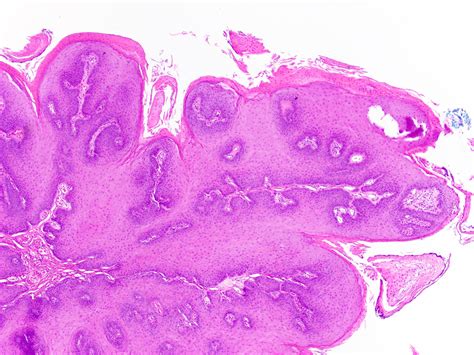

Identifying an Oral Squamous Papilloma often involves observing its distinct morphology. Clinicians look for specific visual cues that differentiate this lesion from other oral pathologies like focal epithelial hyperplasia or squamous cell carcinoma. Because they are exophytic, they grow outward from the surface, often resembling a small cluster of grapes or a delicate cauliflower head.

• Biopsy: The gold standard for diagnosis. A small sample of the tissue is removed and examined under a microscope to confirm the presence of koilocytes—cells characteristic of HPV infection.